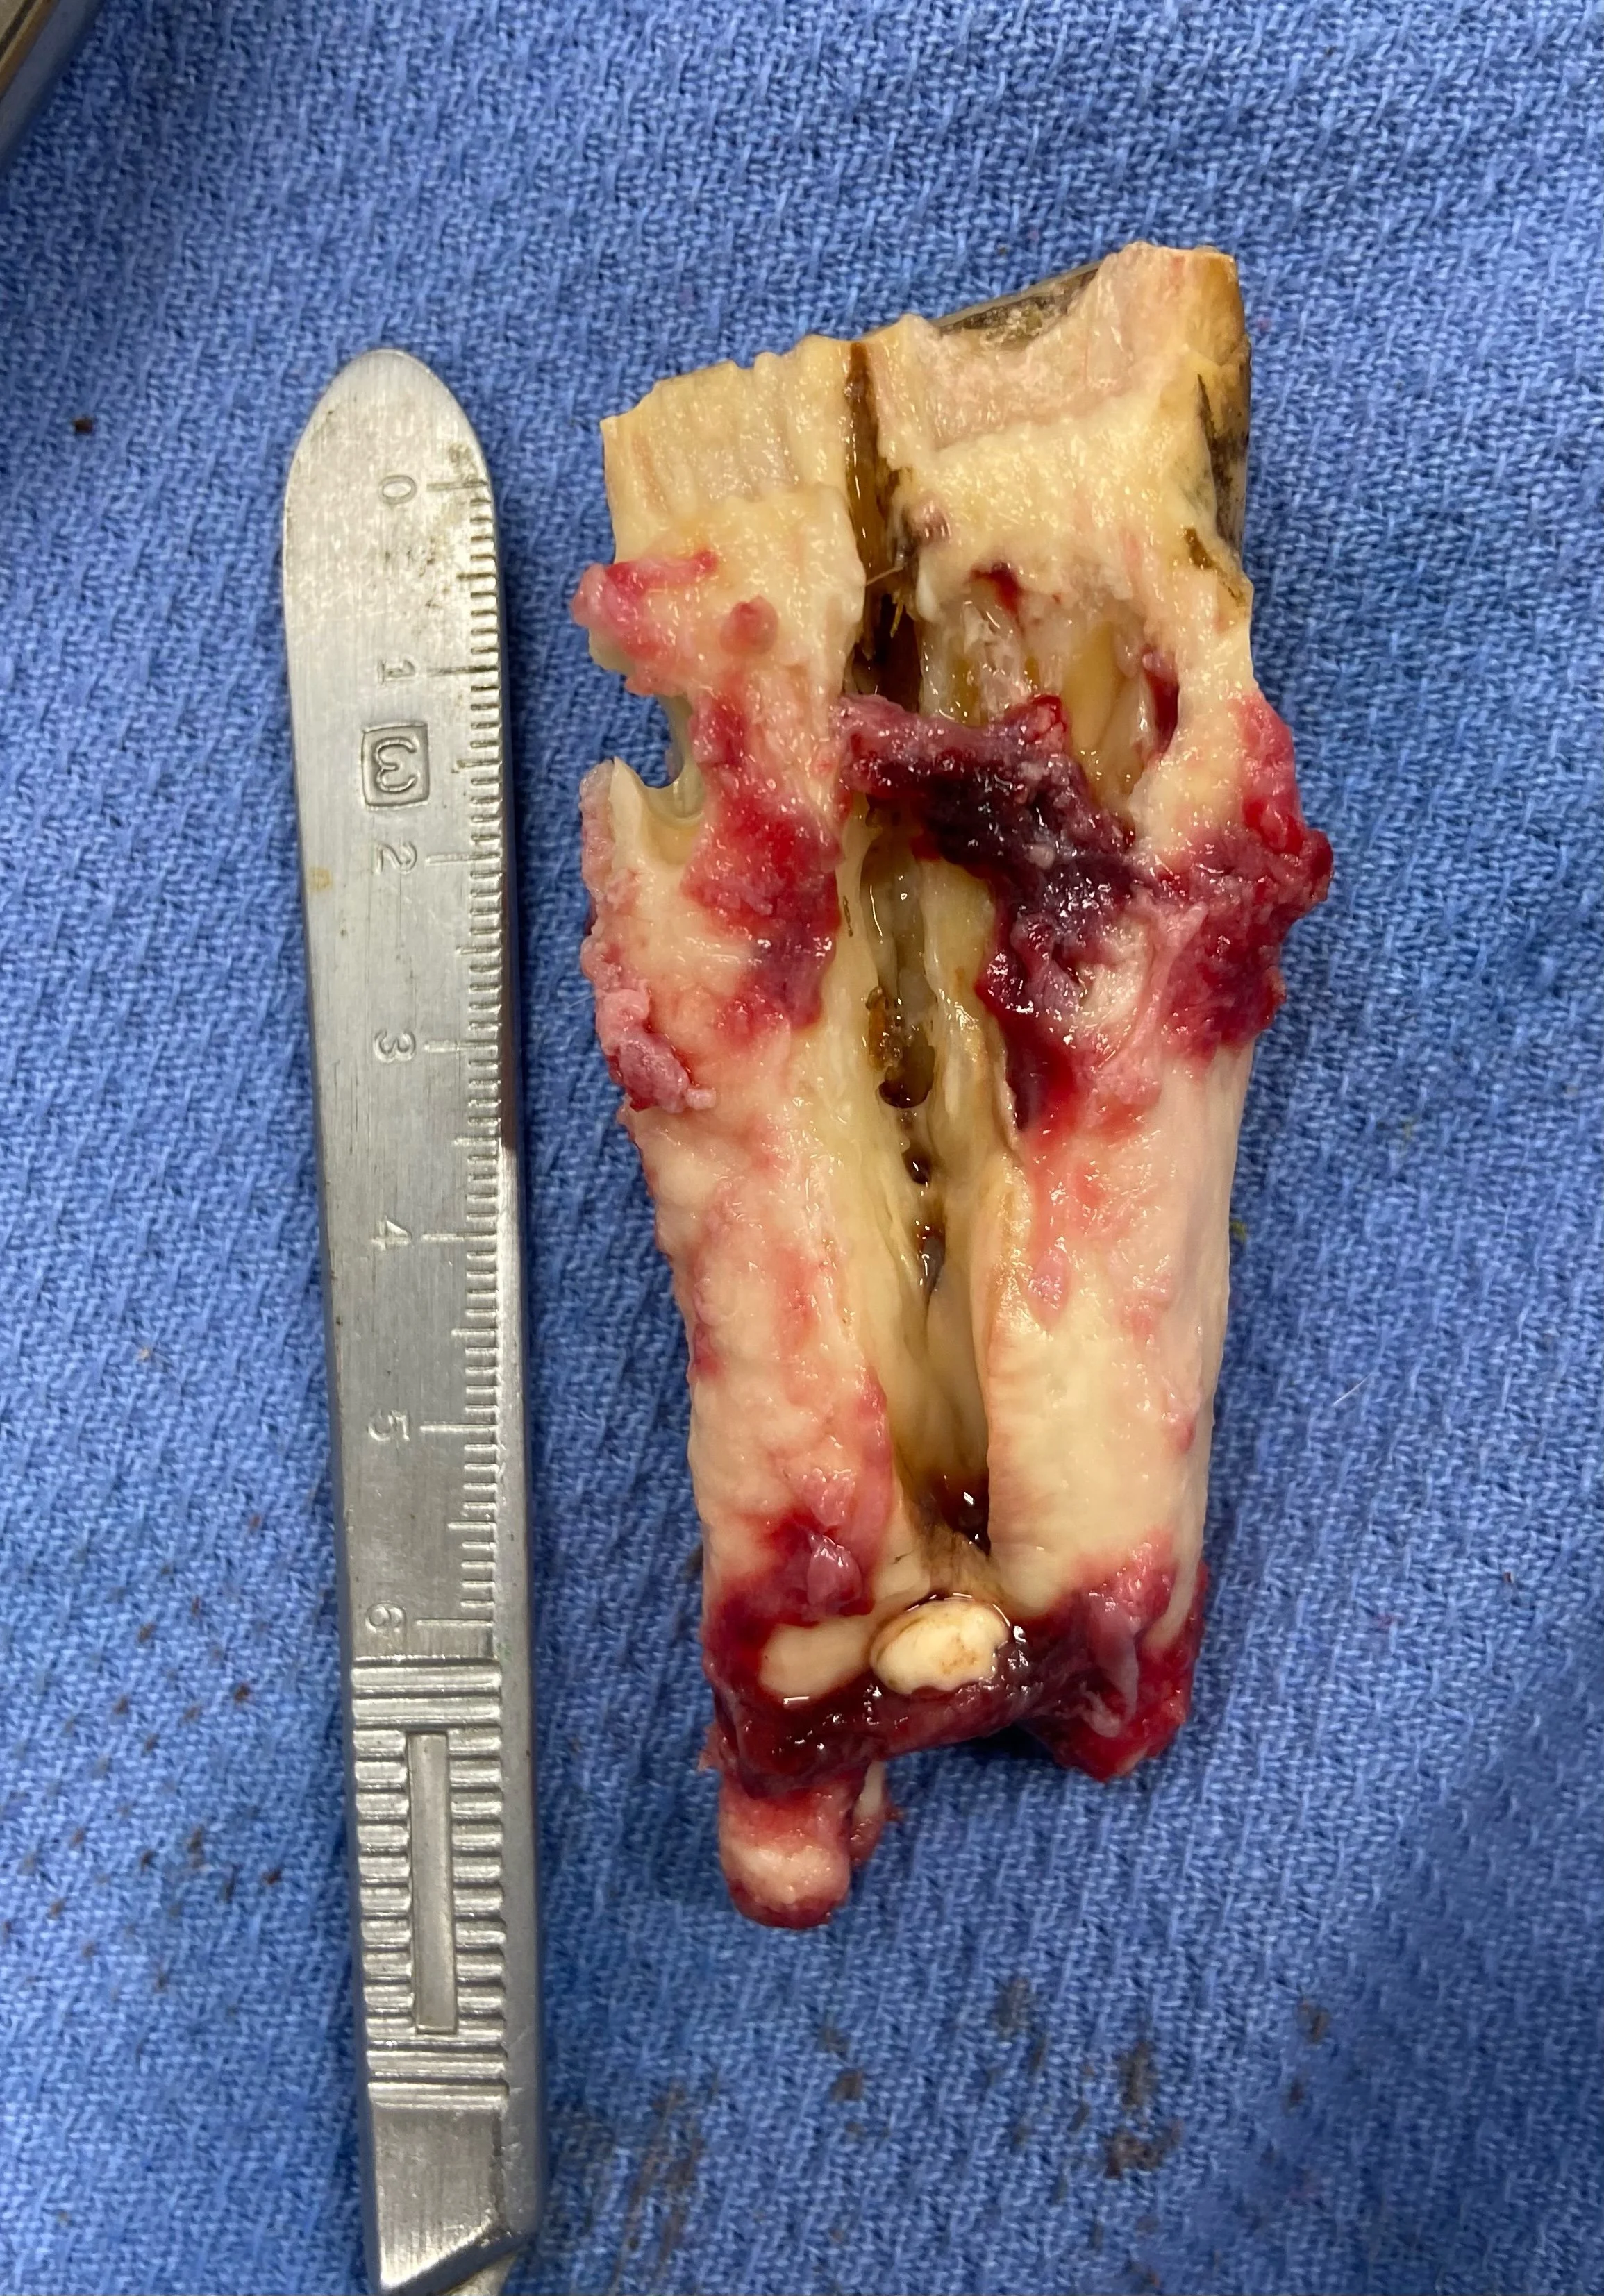

Our goal with equine dentistry is to identify, treat or manage concerns in the mouth to make our patients as comfortable and efficient with mastication as possible. If the dental disease has become too advanced or is not responding to therapies, extraction becomes necessary. Northwest Equine Dentistry provides intra-oral extraction services when that time comes.